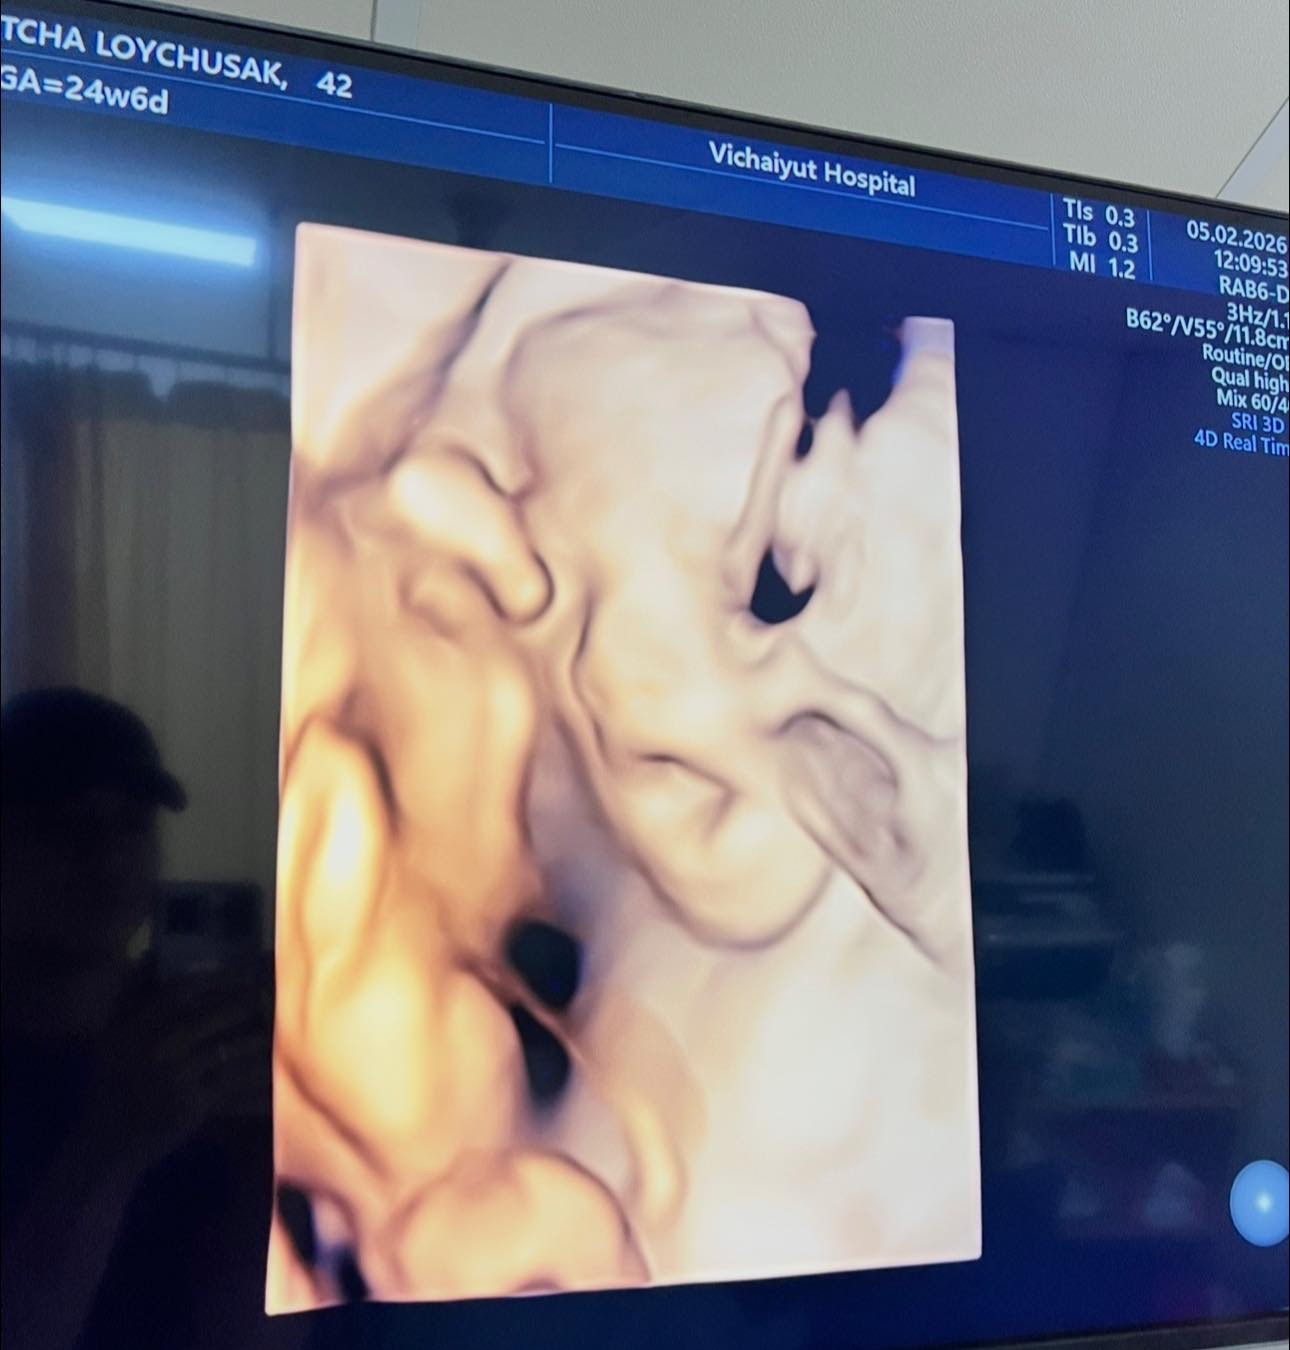

จากภาพอัลตราซาวด์เผยให้เห็นเค้าโครงใบหน้าของน้องมีเมตตาอย่างชัดเจน นอนยิ้มหวานละมุน แถมจมูกโด่งสะดุดตา เรียกได้ว่าน่ารักน่าชังตั้งแต่อยู่ในท้อง โดยพ่อเจมส์เขียนแคปชันด้วยความเอ็นดูว่า “แม่หนูมีเมตตาของฉัน จมูกโด่ง ยิ้มหวาน” พร้อมอัปเดตว่า คุณหมอกล้วย แพทย์ผู้ดูแลครรภ์ครูก้อย ยืนยันว่าลูกน้อยแข็งแรงสมบูรณ์ พัฒนาการเป็นไปตามเกณฑ์ทุกด้าน ก่อนจะปิดท้ายด้วยมุกขำ ๆ สไตล์คุณพ่อว่า “สินค้าเด็กเข้าได้เลยครับ ( ฮาาา…. )” ทำเอาแฟน ๆ เข้ามากดไลก์และคอมเมนต์ชื่นชมความน่ารักของน้องมีเมตตาอย่างล้นหลาม

ด้านคุณแม่คนสวย ครูก้อย นัชชา ก็ไม่น้อยหน้า โพสต์คลิปอัลตราซาวด์ของลูกสาวเช่นกัน พร้อมแคปชันสั้น ๆ ว่า “แม่ว่า…ดูทรงยาว ทรงคมนะ” งานนี้หลายคนอดเดาไม่ได้ว่า น้องมีเมตตาน่าจะได้ความสูงยาวและเค้าโครงคม ๆ มาจากพ่อเจมส์และแม่ก้อยแบบเต็ม ๆ

ก่อนหน้านี้ ครูก้อยเคยให้สัมภาษณ์ว่า การตั้งครรภ์ครั้งนี้แพ้ท้องน้อยมาก อารมณ์ดี มีความสุขตลอด เนื่องจากมีการเตรียมความพร้อมอย่างรอบด้านตั้งแต่ก่อนตั้งครรภ์ ทั้งการจัดการเรื่องงาน โภชนาการ และการออกกำลังกาย เนื่องจากมีภาวะมีบุตรยากจึงมีความเตรียมความพร้อมเป็นพิเศษ เมื่อทุกอย่างลงตัวก็ส่งผลให้ลูกน้อยในท้องอารมณ์ดีตามไปด้วย จนเห็นได้จากภาพอัลตราซาวด์ที่น้องมีเมตตานอนยิ้มหวาน น่าเอ็นดูตั้งแต่อยู่ในท้อง